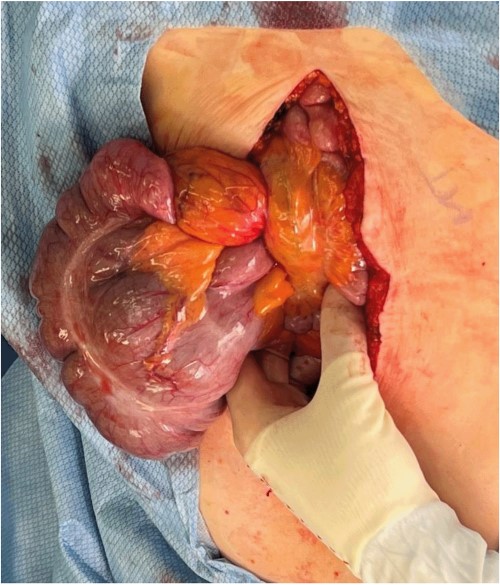

A midline laparotomy was made. A midgut volvulus was encountered immediately upon entering the abdomen and was subsequently reduced from the left upper quadrant. The cecal and ascending colon volvulus had a 540 degree rotation with viable tissues on reduction; however, the ascending colon had a narrow, non-adherent mesentery allowing a point of volvulus while also folding over a Ladd’s band attached to the right lower quadrant of the abdomen. The bowel was then run, and it was confirmed that there was no present ligament of Treitz and that the patient did indeed have congenital malrotation (Fig. 2). There was no retroperitoneal component of duodenum, and it was completely without fixation to other structures. Ladd’s bands were encountered and lysed (Fig. 3).

Evisceration of the midgut volvulus upon entry into the abdomen.